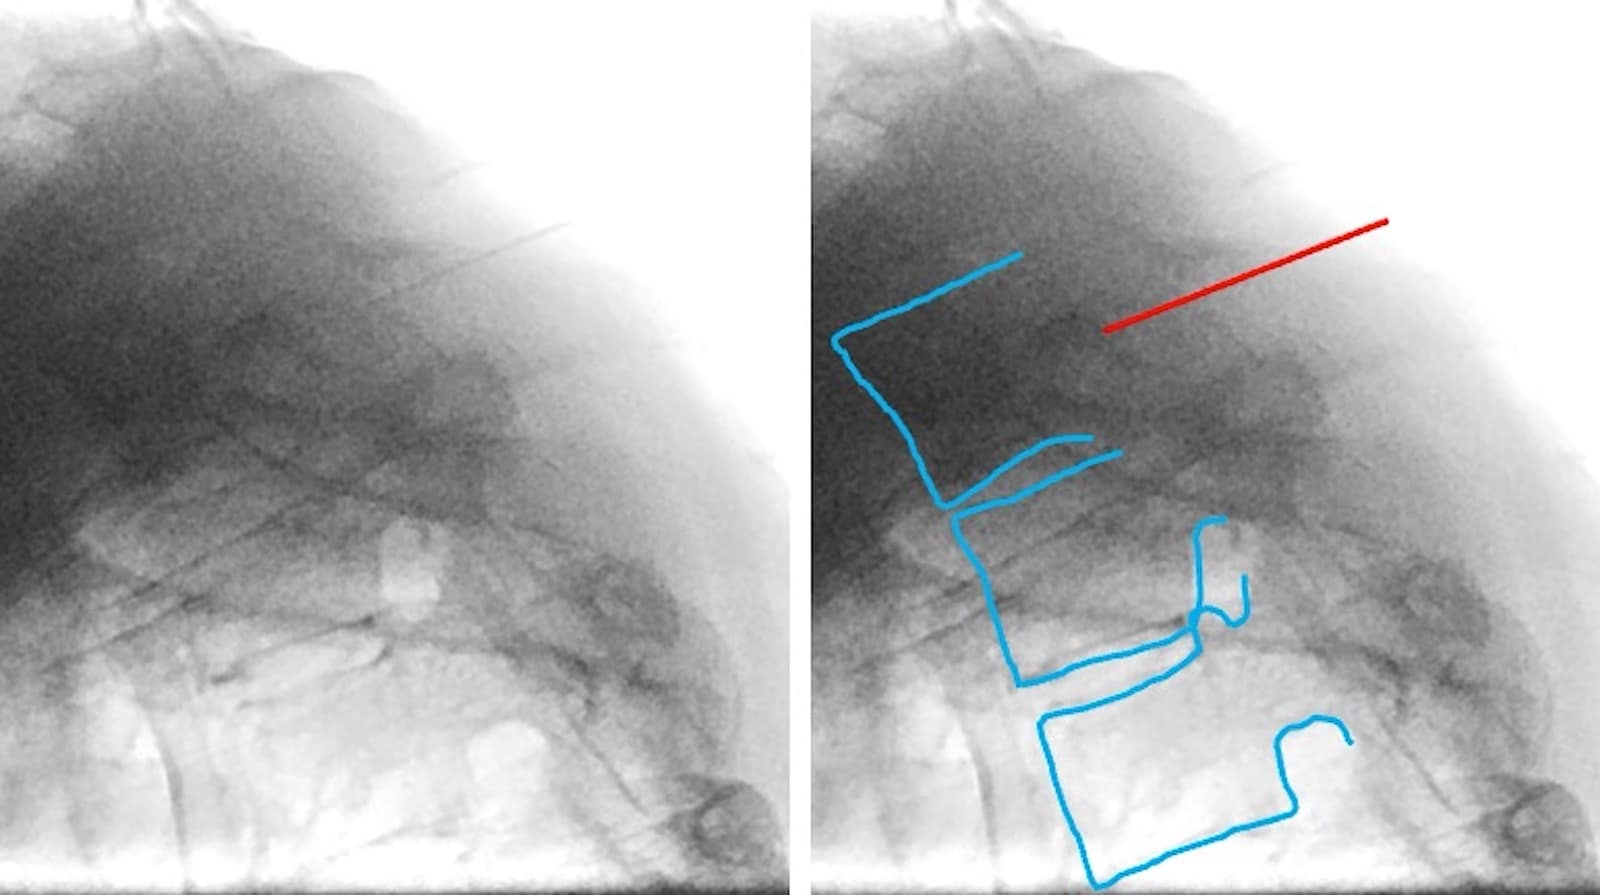

- The needle may pass through the nerve root and reach the vertebral body using only frontal images. In addition to frontal fluoroscopy, lateral fluoroscopy is recommended to verify the needle depth and avoid pneumothorax or mediastinal puncture (Figure 5).

Interpretation of Contrast and Injection of Drugs

The contrast is injected under real-time fluoroscopy once the needle reaches the intervertebral foramen. The tip of the needle should be lateral to the pedicle. Contrast images often show a perineural pattern of the thoracic nerve root block (Figure 5). If the image is appropriate, 0.5–1 mL of 0.5% mepivacaine and 1.65 mg of dexamethasone should be injected. Pulsed or thermal radiofrequency treatments may be applied if necessary. After the nerve block, vital signs should be monitored, and bed rest should be ensured for 45 minutes.

Red line = needle; blue line = vertebrae.